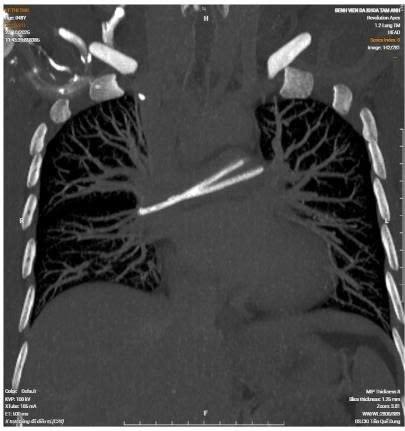

Trong một lần đi khám tầm soát tại cơ sở y tế tư nhân, bệnh nhân được chỉ định chụp CT ngực có tiêm thuốc cản quang. Kết quả ghi nhận hình ảnh một dị vật nằm trong tim, vắt ngang tại vị trí động mạch phổi hai bên. Trước nguy cơ biến chứng, bệnh nhân được tư vấn cần can thiệp lấy dị vật và đã quay lại bệnh viện công lập, nơi từng điều trị ung thư trực tràng, để tiếp tục thăm khám.

Tại đây, kết quả chụp X-quang ngực xác định ống truyền hóa chất đã bị đứt. Một đoạn vẫn còn nằm dưới da, trong khi đoạn còn lại đã di chuyển theo dòng máu vào tim và mắc kẹt tại động mạch phổi. Bệnh nhân được chỉ định rạch da để lấy phần ống còn sót lại dưới da; riêng đoạn trôi vào tim được chuyển đến Bệnh viện Quân y 175 để tiếp tục can thiệp chuyên sâu.

Tại Bệnh viện Quân y 175, ê-kíp Khoa Can thiệp Tim mạch đánh giá đây không phải là ca bệnh phức tạp về mặt kỹ thuật. Tuy nhiên, điểm đặc biệt của trường hợp này là dị vật đã di chuyển rất sâu, nằm sát vùng chia nhánh động mạch phổi, vị trí cực kỳ hiếm gặp trên lâm sàng.